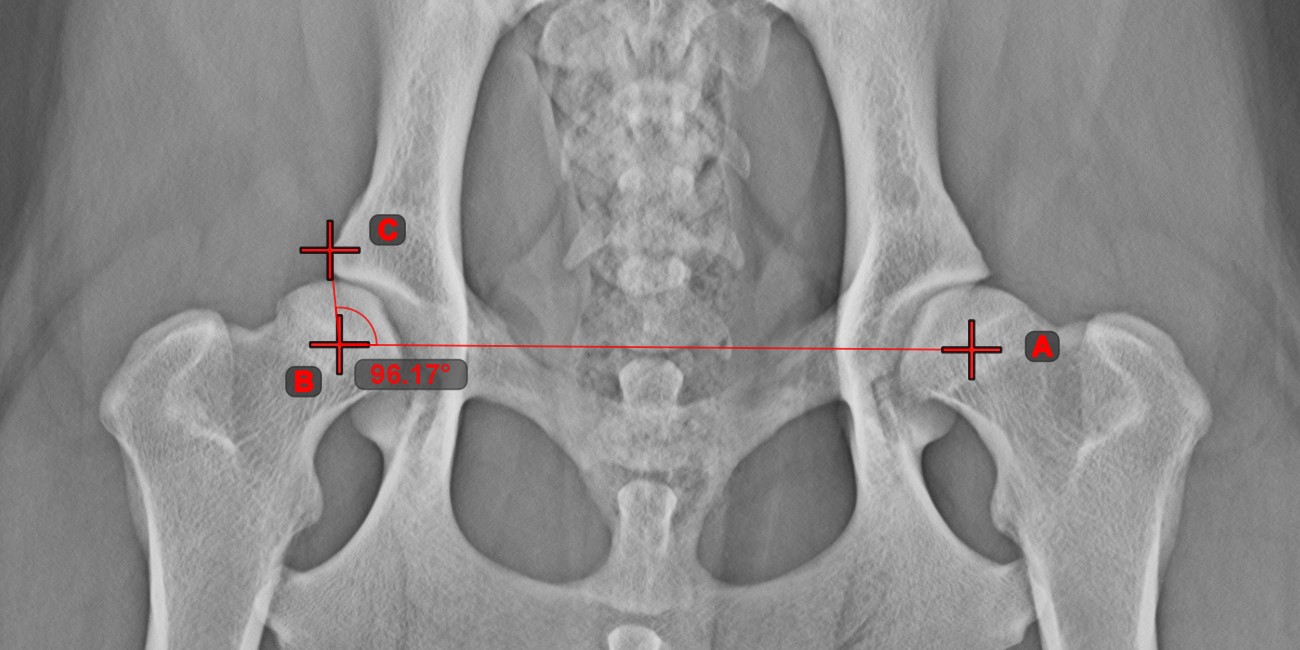

Winkel zwischen Linien¶

Berechnen Sie den Winkel zwischen zwei unabhängigen oder sich schneidenden Linien mit dem Werkzeug Winkel zwischen Linien

.

Wählen Sie das Werkzeug aus der linken Symbolleiste aus und weisen Sie es einer der verfügbaren Maustasten zu. Beginnen Sie, indem Sie die erste Linie aus den bereits in der Szene gezeichneten Linien auswählen oder Start- und Endpunkt setzen, um die Linie zu erstellen. Wiederholen Sie die gleichen Schritte für die zweite Linie der Messung. Der Winkel zwischen den beiden Linien wird automatisch berechnet.

Ändern Sie die Start- und Endpunkte beider Linien mit dem Werkzeug Objekt auswählen/verschieben

. Der Winkel zwischen den beiden Linien wird automatisch neu berechnet.

Informationen

Wenn sich zwei Linien nicht direkt schneiden, wird der Winkel ihrer verlängerten Projektionen in der Szene berechnet.